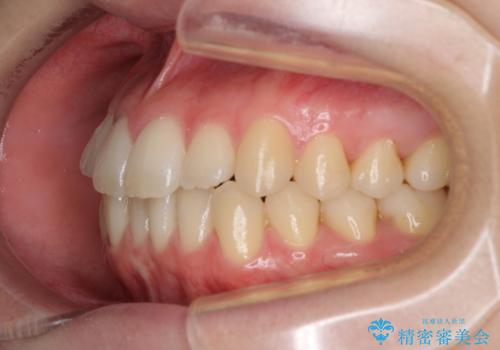

気になる前歯を整えたい インビザライン・ライトでの矯正治療

- ちょっとしたデコボコを整えたいとのことで来院された患者様です。

歯列不正は軽微であったため、インビザライン・ライトにより、費用を抑えて矯正治療を行うこととしました。

上下前歯の捻れが改善され、患者様には大変満足していただきました。